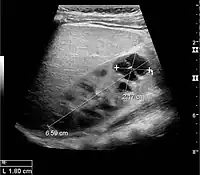

Masses are seen as a distortion of the normal renal architecture. Most renal masses are simple cortical renal cysts with a round appearance and a smooth thin capsule encompassing anechoic fluid. The incidence increases with age, as at least 50% of people above the age of 50 have a simple cyst in one of the kidneys. Cysts cause posterior enhancement as a consequence of reduced attenuation of the ultrasound within the cyst fluid (Figure 5). The simple cyst is a benign lesion, which does not require further evaluation.[1]

Complex cysts can have membranes dividing the fluid-filled center with internal echoes, calcifications or irregular thickened walls. The complex cyst can be further evaluated with Doppler US, and for Bosniak classification and follow-up of complex cysts, either contrast-enhanced ultrasound (CEUS) or contrast CT is used (Figure 6). The Bosniak classification is divided into four groups going from I, corresponding to a simple cyst, to IV, corresponding to a cyst with solid parts and an 85–100% risk of malignancy.[1] In polycystic kidney disease, multiple cysts of varying size in close contact with each other are seen filling virtually the entire renal region. In advanced stages of this disease, the kidneys are enlarged with a lack of corticomedullary differentiation (Figure 7).[1]